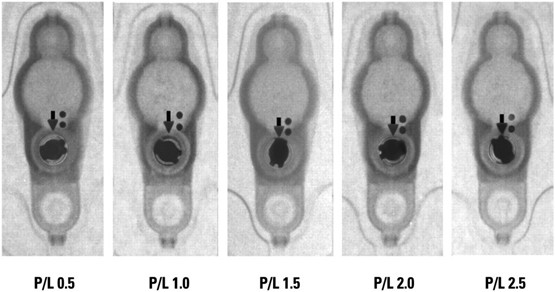

典型的な特発性正常圧水頭症の画像所見 (MRI 左:軸位断 右:冠状断)

* 脳室拡大

** シルビウス裂開大

〇 高位円蓋部脳溝狭小化所見